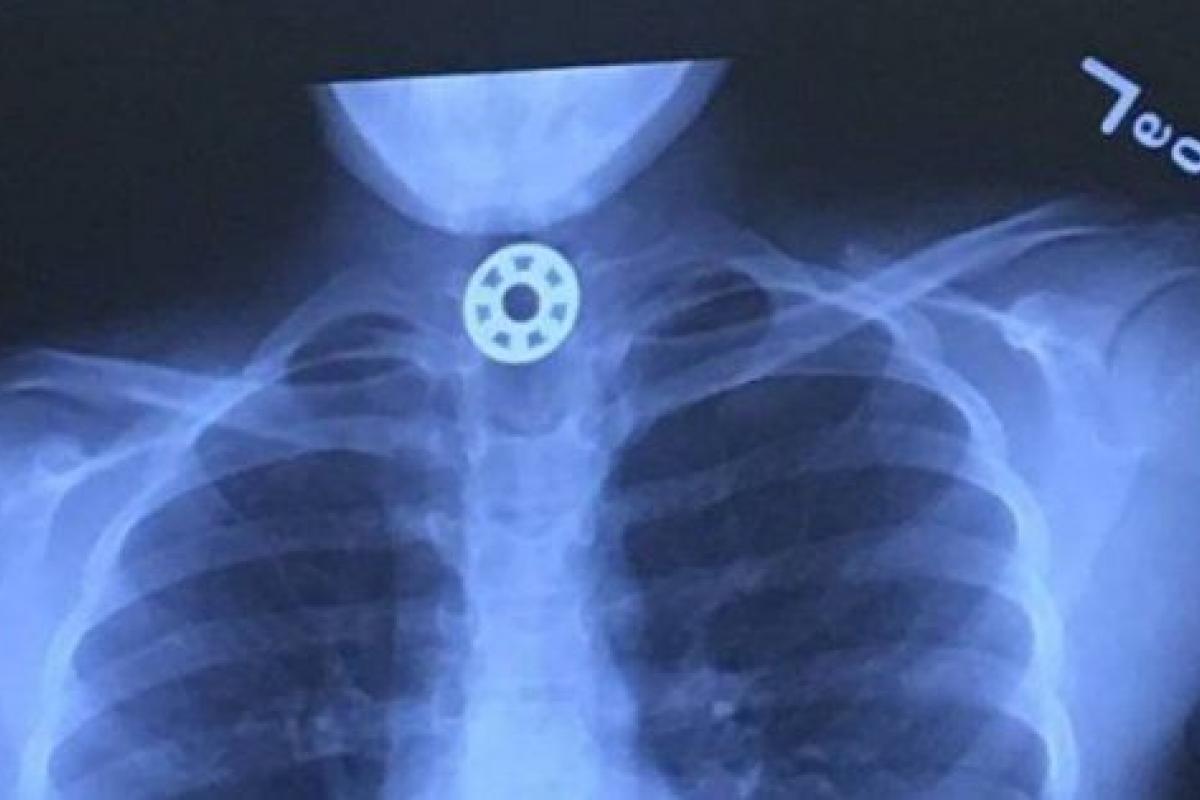

Joenic trató de aplicar la maniobra de Heimlich, pero sin éxito: el objeto seguía encajado en la garganta de la niña. Entonces la madre la llevó al hospital infantil de Texas, donde le hicieron una radiografía que mostraba que la anilla del spinner se encontraba en su esófago.